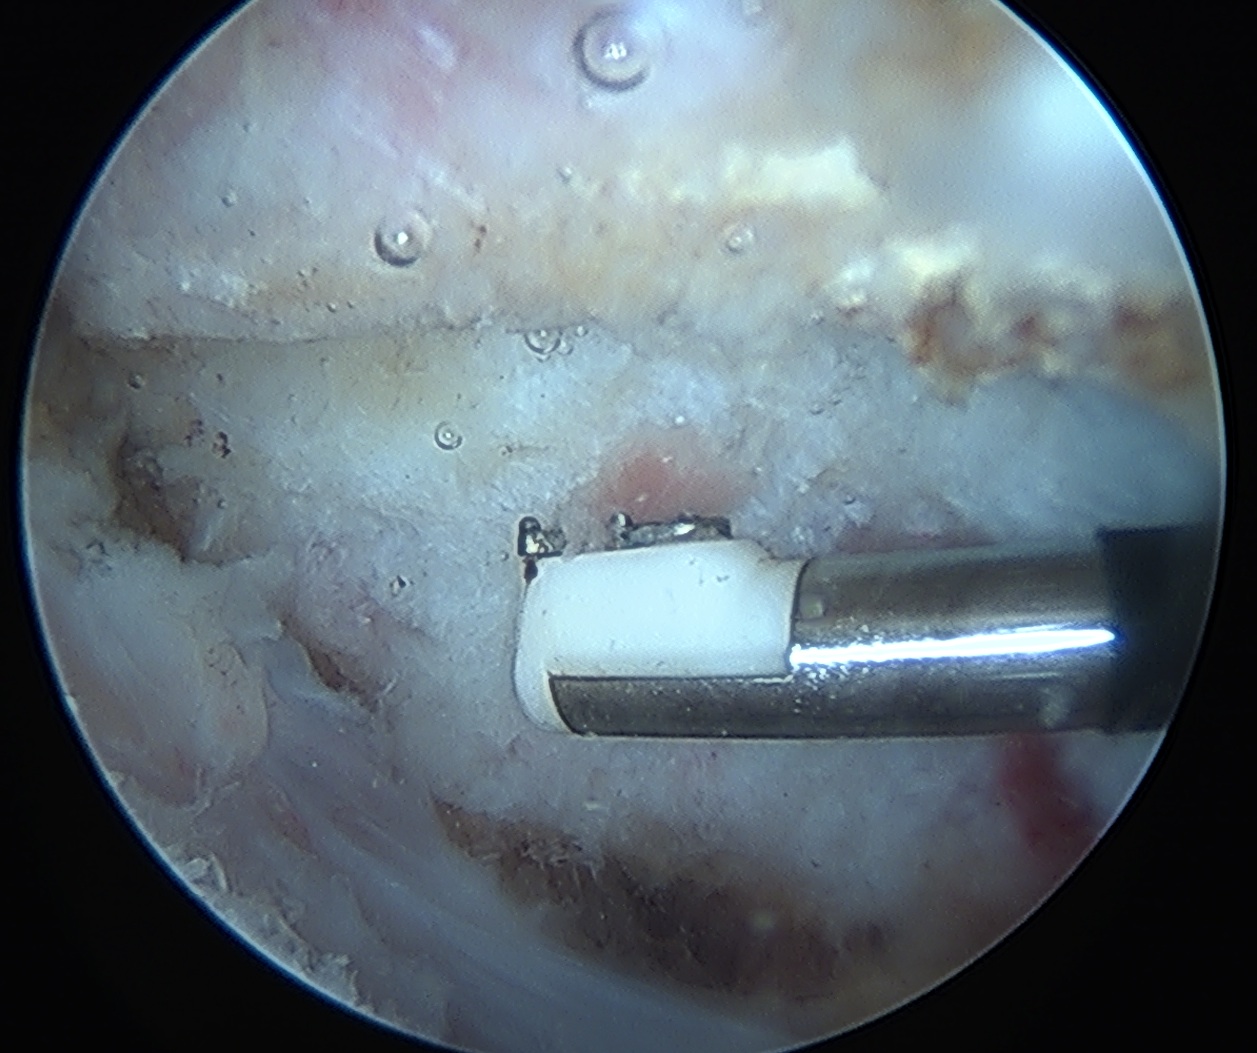

Arthroscopic - leaves deltoid attach intact

Vumedi video arthroscopic excision of os acromiale